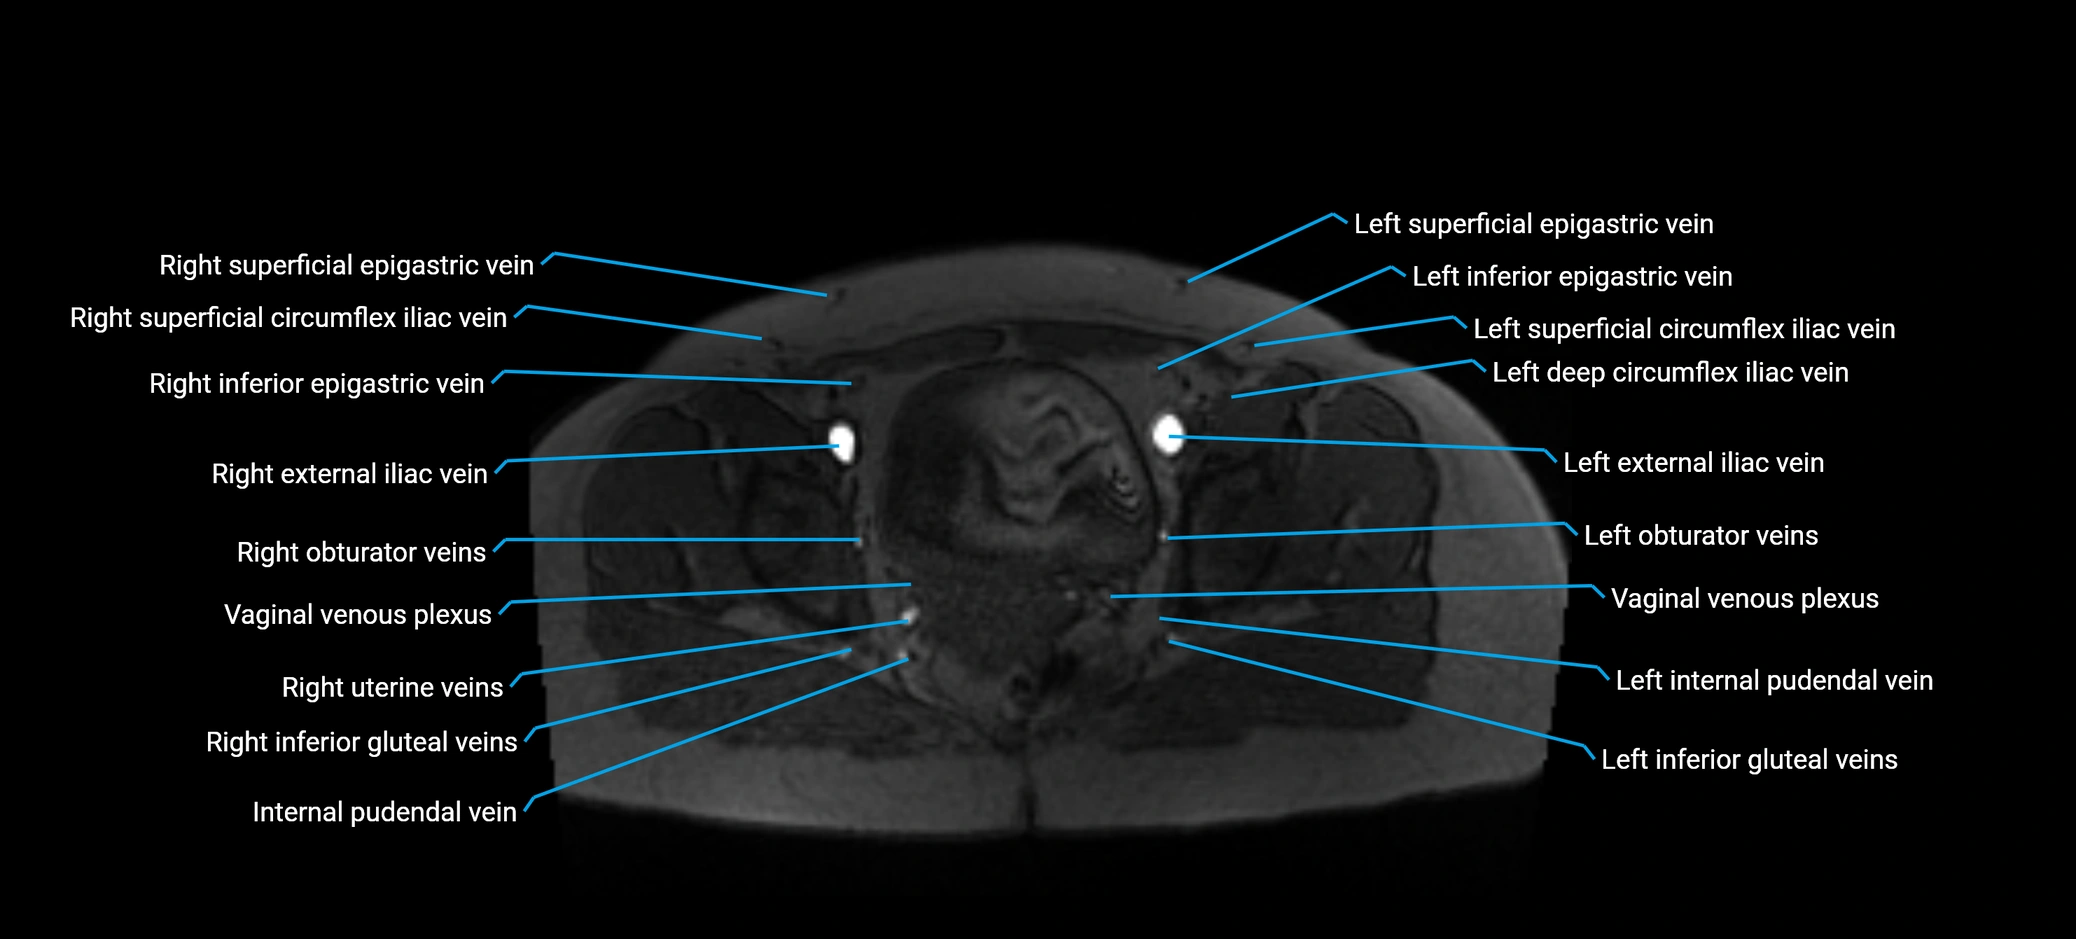

MRI image

image